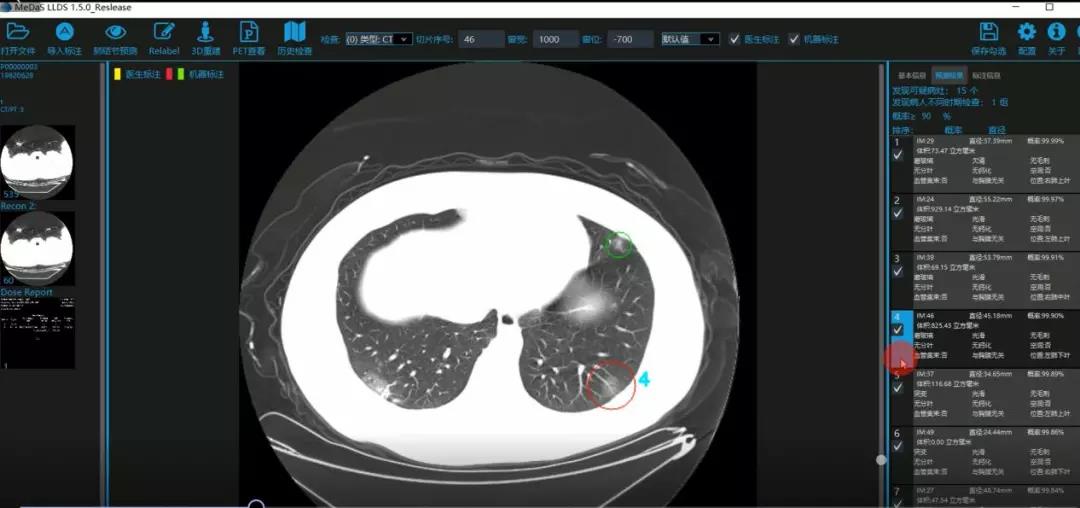

医护人员的好帮手:基于深度学习的新冠肺炎早期检测筛查系统

西电kaiyun登录中国入口登录智能软件与系统新技术研究所副教授张亮的爱人是西安交通大学第二附属医院抗疫一线的影像科医生,疫情发生以来,他们讨论最多的就是新型冠状病毒感染者的早期诊断问题。作为一名医护家属,身为高校科研工作者,张亮深知快速准确地诊断新冠肺炎早期患者对控制和防治疫情的重要性和挑战性。他与团队成员主动出击,通过远程网络会议,在前期医学影像处理的研究基础上加速科研攻关,反复讨论方案,屡次设计模型,与上海宽带技术及应用工程研究中心、上海交通大学医学院附属瑞金医院等合作单位的人员多次标注整理患者肺部CT影像数据到深夜。与此同时,他们依托上海瑞金医院、西安交通大学第二附属医院等的新冠肺炎疑似、确诊患者肺部CT影像,通过综合分析新冠肺炎患者的肺部CT影像特点(磨玻璃、体积大小、位置等特征),张亮团队加快技术攻关,设计开发了基于深度学习的新型冠状病毒的早期检测筛查模型系统。

对应新冠肺炎CT病灶检测效果

令人欣喜的是,通过对实际门诊数据排查测试,该模型可以减轻医护人员近80%的工作量,新冠肺炎患者的检测召回率超过95%。目前,模型系统正在进行最后的调试工作,很快投入到“战疫”一线,缓解医护人员紧缺、确诊检测工作耗时较长等问题,减少医护人员的工作时间和劳动强度,提高工作效率。